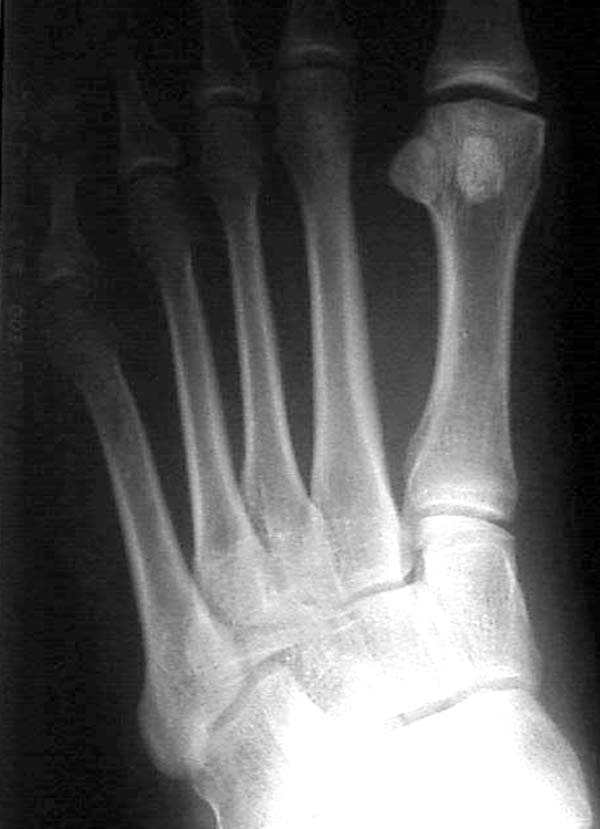

По снимкам нельзя исключить разрыв связки Лисфранка (связки между медиальной клиновидной костью и основанием второй плюсневой). Помогает в диагностике клиника (наличие изолированной гематомы на подошвенной поверхности стопы) и МРТ картина. Если связка повреждена - необходимо оперативное лечение.

По первому снимку, не видя больного, мог бы заподозрить перелом основания 3-й плюсневой кости. Поэтому избрал бы тактику консервативного лечения, как при переломе плюсневых костей без смещения!

Здесь КТ и сравнительные снимки стопы под нагрузкой.

Диагностировано повреждение медиальной и латеральной колонны.